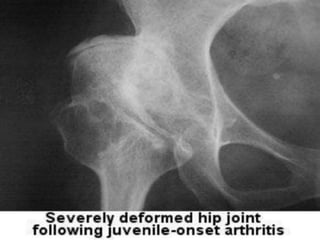

• Deformity

Advanced rheumatoid arthritis.

Small muscle wasting, subluxation and ulnar deviation at the

metacarpophalangeal joints, boutonnière deformities at the

ring and little fingers, and swelling and deformity of the

wrist.